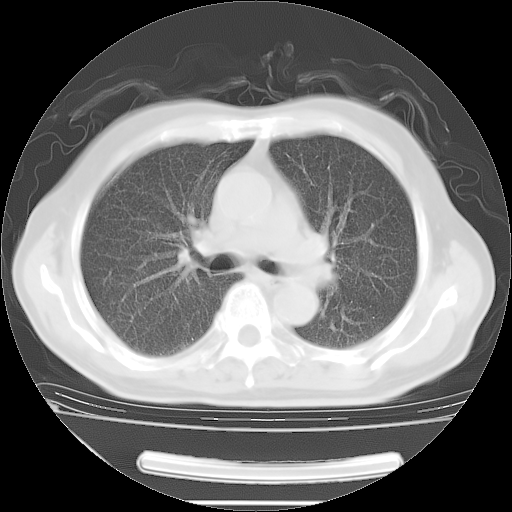

今天复查肺部CT,发现双肺广泛磨玻璃样改变。所以我把3月19日和5月9日相隔50天的肺部CT上传。请大家会诊。

5月9日肺部CT(在4月27日齐鲁医院肺部CT描述部分肺组织磨玻璃样改变,12天后肺组织广泛磨玻璃样改变)

2009年5月9日肺部CT

大致读了系列胸部CT:纵隔窗无明显异常,肺窗:从4、27至今:主要是双肺中下野外带可见毛玻璃样改变,目前处于急性肺泡炎阶段,至于原因考虑1、结替组织或胶原血管性疾病所致?2、恶性疾病如恶组在肺部所致的表现或细支气管肺泡癌?3、药物或其它原因如肺蛋白沉着症所致肺泡炎目前不太可能?总之,明天就去请我院的呼吸科、感染科、血液科和临免专家会诊哈。